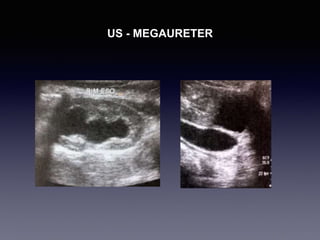

MEGAURETER

US - MEGAURETER